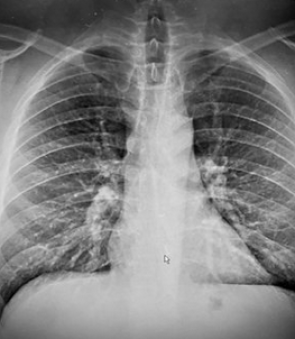

His son suggested that Mr Gauthier had swallowed the earbud, which was later confirmed by an X-ray at a local emergency clinic.

The small plastic device was lodged in his lower oesophagus, part of the alimentary canal that connects the throat to the stomach